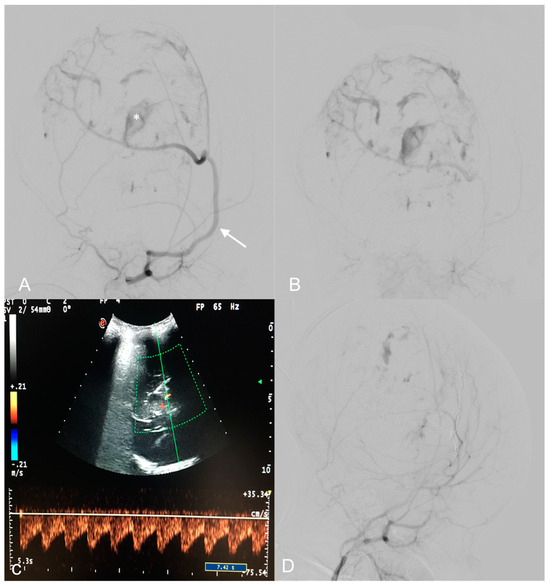

2.2. Endovascular Embolization and Surgical Treatment